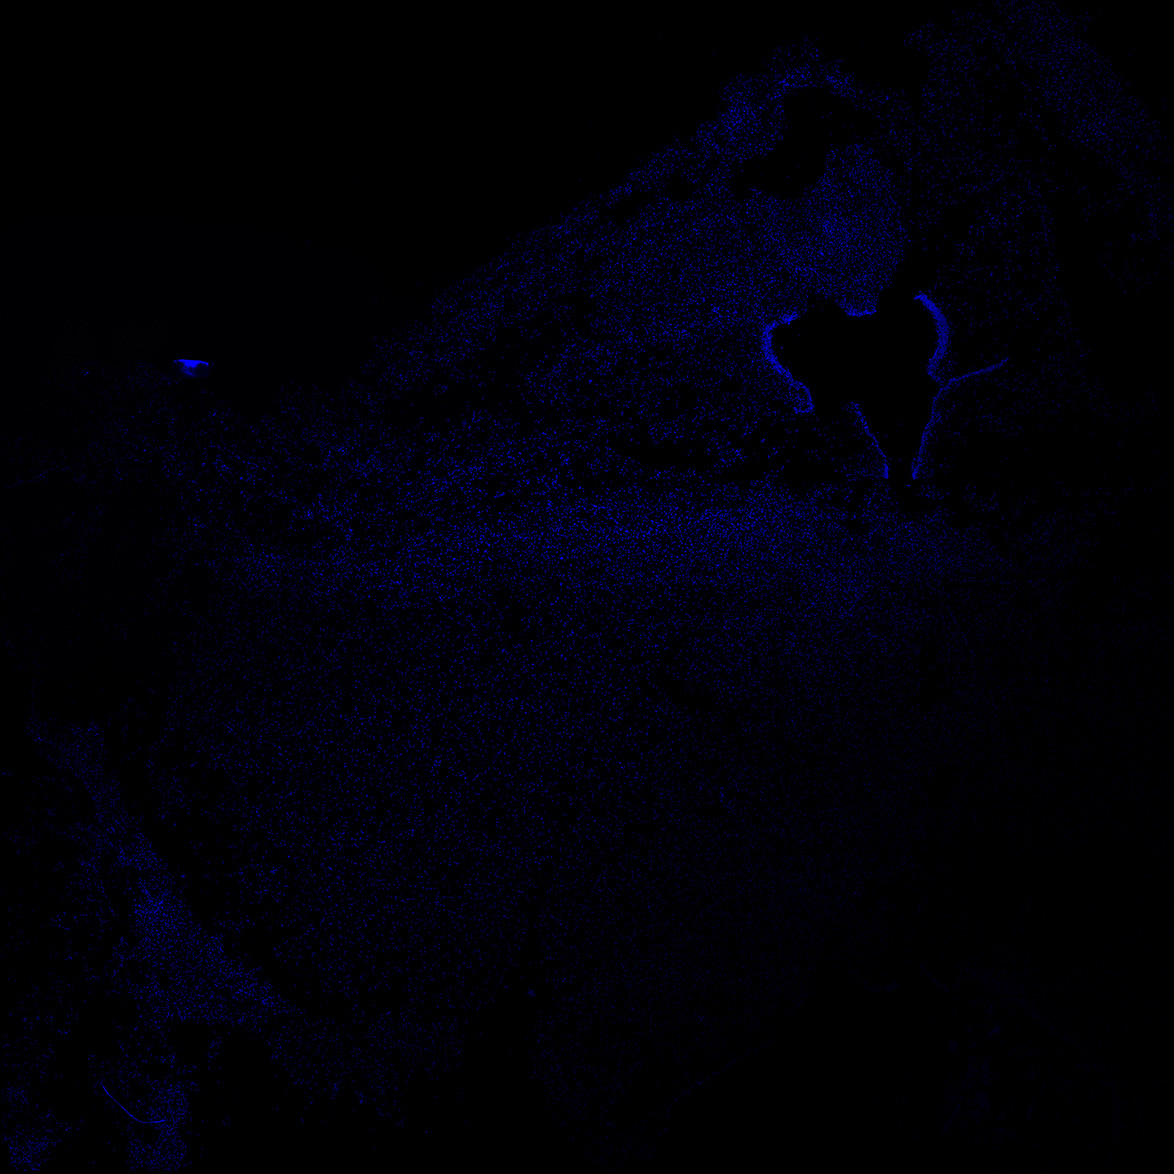

DAPI

6PCW human midbrain